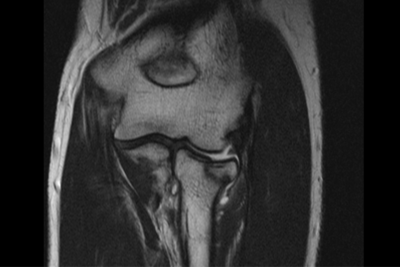

МРТ локтевого сустава

МРТ локтевого сустава применяется для исследования костей, мягких тканей и кровеносных сосудов верхней конечности в области локтя. Магнитно-резонансная томография предполагает проведение процедуры с помощью томографа, который создает магнитное поле и преобразует реакцию организма в изображение, появляющееся на экране компьютера. МРТ локтевого сустава позволяет выявить патологический процесс даже на начальной стадии его развития.

МРТ локтя проводится с целью обнаружения патологических процессов и их особенностей. Сканирование затрагивает зону не только локтя, но и нижней части предплечья.

В результате томографии удается выявить:

- трещины и переломы;

- абсцессы и бурситы;

- новообразования и инфекционные процессы;

- поражение нервов;

- эпикондилит, синовит или остеонекроз;

- повреждения сухожилий, хрящей и связок;

- артрозы и артриты.

На сегодняшний день магнитно-резонансная томография признана самым информативным и безопасным способом определения патологий костной и мягких тканей локтя и других частей тела человека.